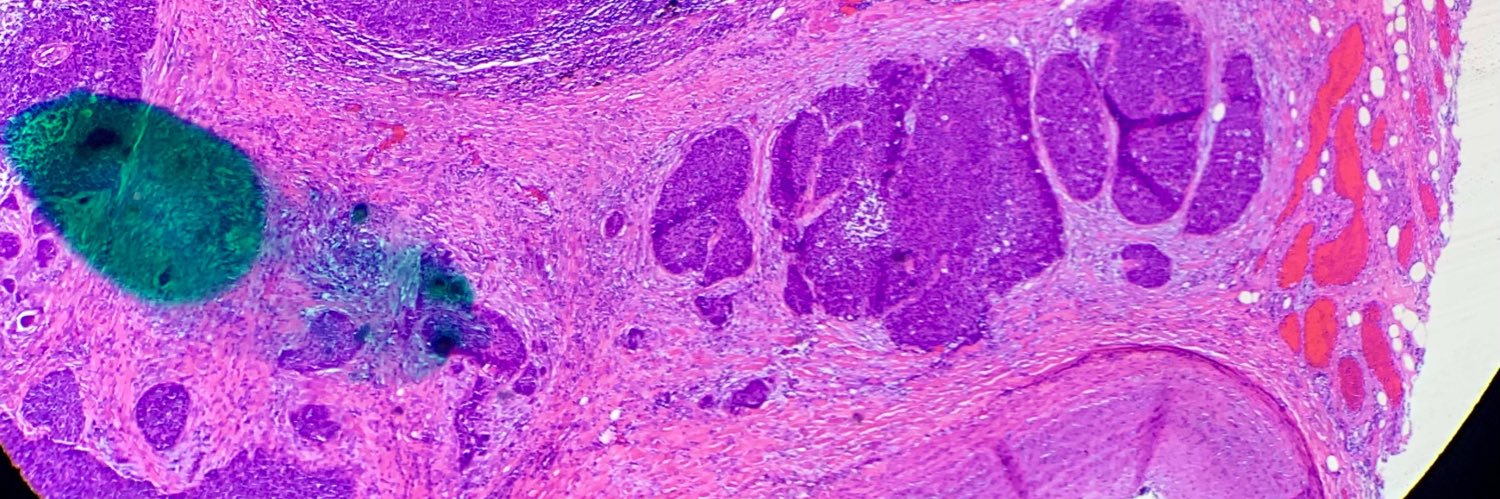

I am passionate about surgical pathology and hematological malignancies!